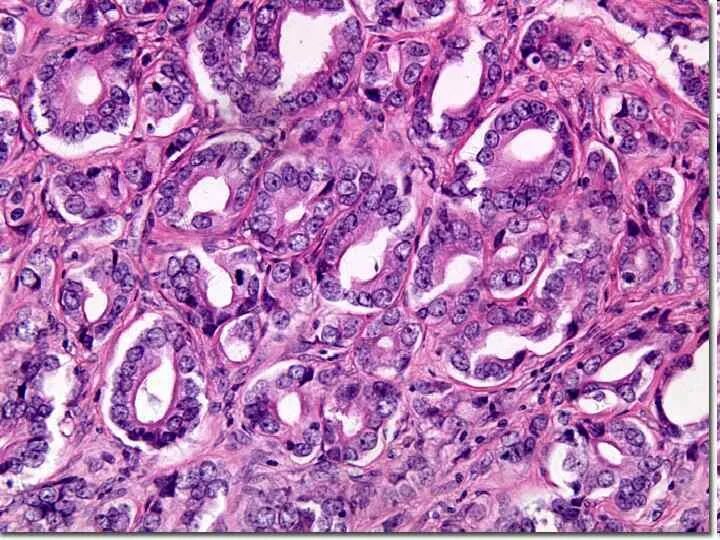

Диффузная гиперплазия что это